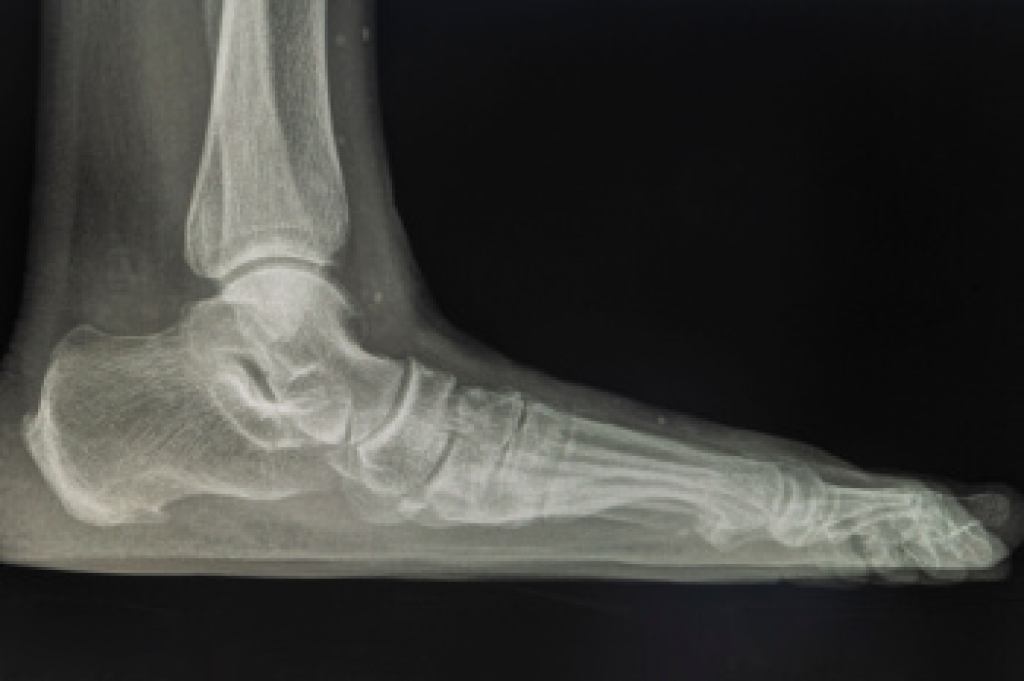

Burn injuries on the feet can occur from scalding liquids, stepping on hot surfaces, or chemical exposure. They are common in people who walk barefoot or work in environments with high heat or hazardous materials. These burns can be particularly concerning due to the foot's thinner skin and role in mobility. Immediate care involves cooling the burn under lukewarm water and gently cleaning it to remove debris. Cover the wound with a sterile, non-stick bandage and elevate the foot to reduce swelling. If you have sustained a burn foot wound, it is strongly suggested that you promptly contact a podiatrist to assess the burn's severity, prevent infection, and develop a treatment plan. Burns can lead to complications, such as infections or tissue damage, so care from this type of doctor is essential for effective healing and recovery.

Wound care is the practice of taking proper care of a wound. This can range from the smallest to the largest of wounds. While everyone can benefit from proper wound care, it is much more important for diabetics. Diabetics often suffer from poor blood circulation which causes wounds to heal much slower than they would in a non-diabetic.

While it may not seem apparent with small ulcers on the foot, for diabetics, any size ulcer can become infected. Diabetics often also suffer from neuropathy, or nerve loss. This means they might not even feel when they have an ulcer on their foot. If the wound becomes severely infected, amputation may be necessary. Therefore, it is of the upmost importance to properly care for any and all foot wounds.

The best way to care for foot wounds is to prevent them. For diabetics, this means daily inspections of the feet for any signs of abnormalities or ulcers. It is also recommended to see a podiatrist several times a year for a foot inspection. If you do have an ulcer, run the wound under water to clear dirt from the wound; then apply antibiotic ointment to the wound and cover with a bandage. Bandages should be changed daily and keeping pressure off the wound is smart. It is advised to see a podiatrist, who can keep an eye on it.